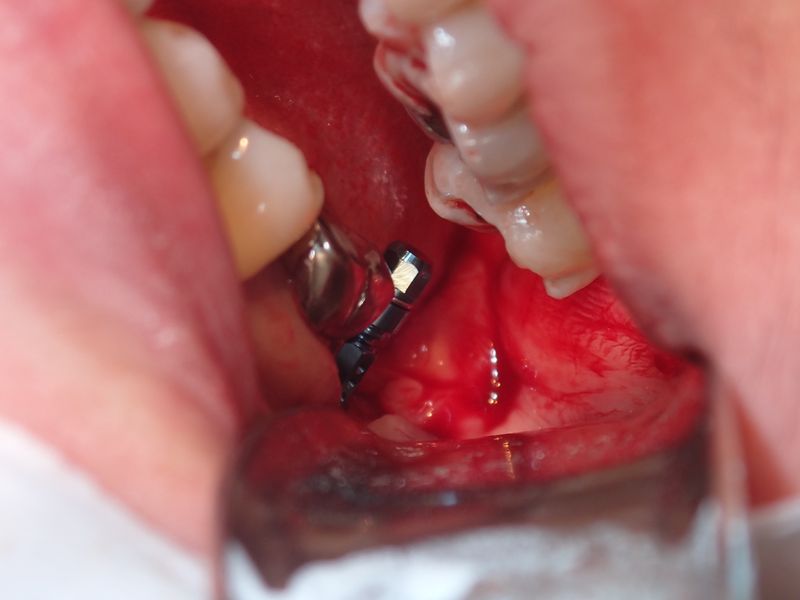

P9160003.JPG

Olympus TG-6

1/100s f/4.9 at 18.0mm iso200